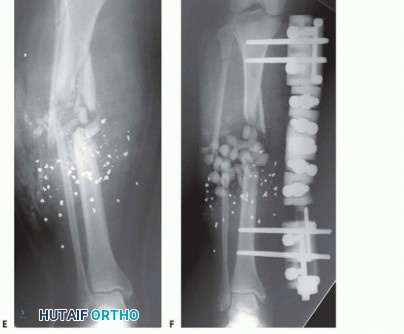

Open tibial diaphyseal fractures are primarily candidates for closed intramedullary nailing, but there are occasions when external fixation is indicated. External fixation is favored when there is significant contamination and severe soft tissue injury or when the fracture configuration extends into the metaphyseal-diaphyseal junction or the joint itself, making intramedullary nailing problematic. 533 The choice of external fixator type depends on the location and complexity of the fracture as well as the type of wound present when dealing with open injuries. The less stable the fracture pattern (ie, the more comminution), the more complex a frame needs to be applied to control motion at the bone ends. If possible, weight bearing should be a consideration. If periarticular extension or involvement is present, the ability to bridge the joint with the frame provides satisfactory stability for both hard and soft tissues. It is important that the frame be constructed and applied to allow for multiple débridements and subsequent soft tissue reconstruction. This demands that the pins are placed away from the zone of injury to avoid potential pin site contamination with the operative field. Fractures treated with external fixation heal with external bridging callus. External bridging callus is largely under the control of mechanical and other humoral factors and is highly dependent on the integrity of the surrounding soft tissue envelope. This type of fracture healing has the ability to bridge large gaps and is very tolerant of movement. Micromotion with the external fixator construct has been found to accentuate fracture union. It results in the development of a large callus with formation of cartilage due to the greater inflammatory response caused by increased micromovement of the fragments. There appears to be a threshold at which the degree of micromotion becomes inhibitory to this overall remodeling process, however, so hypertrophic nonunion can result from an unstable external frame. Temporary spanning fixation for complex articular injuries is used routinely. The ability to achieve an initial ligamentotaxis reduction substantially decreases the amount of injuryrelated swelling and edema by reducing large fracture gaps. It is important to achieve an early ligamentotaxis reduction: A delay of more than a few days will result in an inability to disimpact and adequately reduce displaced metaphyseal fragments with distraction alone. Once the soft tissues have recovered, definitive open reconstruction can be accomplished with relative ease as the operative tactic can be directed to the area of articular involvement. 13 Application of these techniques in a polytrauma patient is valuable when rapid stabilization is necessary for a patient in extremis. Simple monolateral or monotube fixators can be placed rapidly across long bone injuries, providing adequate stabilization to facilitate the management and resuscitation of the polytrauma patient ( FIG 3).

SURGICAL MANAGEMENT The surgical decisions relate to the configuration of the external device to be applied. These generally will fall into two categories of treatment options. The first category is a temporary device intended to allow the soft tissues to recover or the patient's overall condition to improve until definitive fixation of the injury can be safely carried out. Temporary frames include knee- or ankle-spanning fixators used in cases of periarticular injuries requiring ligamentotaxis reduction and relative stabilization and simple frames spanning a tibial shaft fracture in the case of a polytrauma patient who needs emergent stabilization of injuries. These frames are later converted to intramedullary nails once the patient can undergo additional surgery. 6 They are simplistic and not intended for long-term treatment times. Definitive treatment fixators are primarily applied to diaphyseal injuries with severe soft tissue compromise (open and closed).